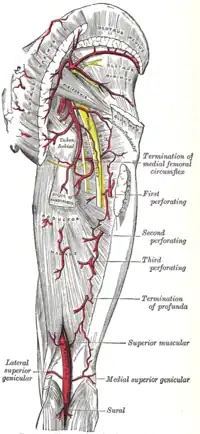

Les muscles du bassin. Les artères de la région fessière et fémorale postérieure.

Les artères de la région fessière et fémorale postérieure. Coupe sagittale du bassin montrant le plexus sacré.

Vascularisation

Le muscle piriforme est vascularisé par les artères glutéales et sacrales.